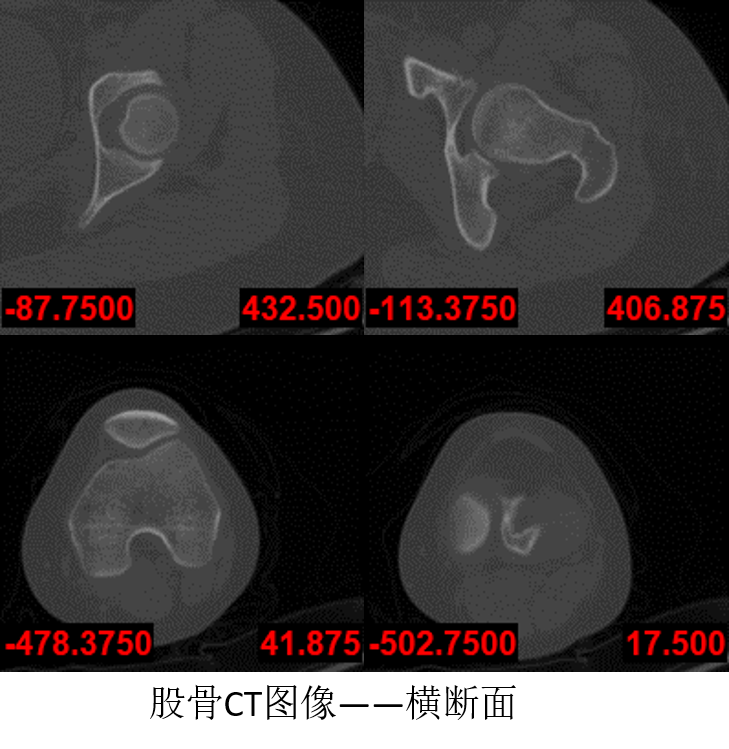

本实验是对髋骨近端的股骨进行分割,下图是股骨CT图像的部分图像,目前股骨分割所面临的问题主要有以下几点: